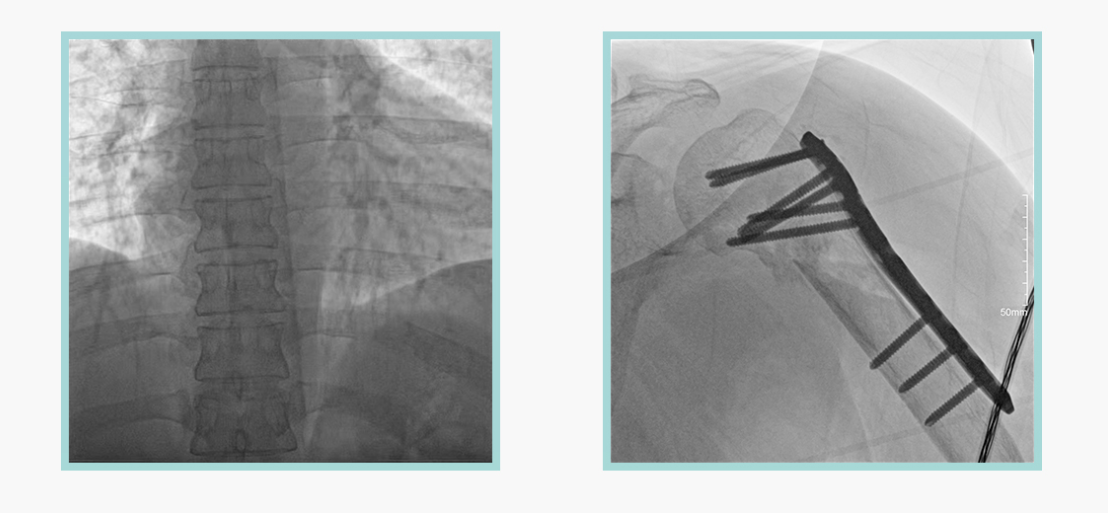

作為全球X線機的主要參與者,安健科技在數字化X線產品線實現全線動態化之外,在移動C臂X光機產品線領域推出全新平板移動C臂產品:悅畫。隨著國家“千縣工程”提升基層醫療衛生服務能力,外科對于手術介入引導設備的需求劇增。對于一臺優秀的移動C臂X線機而言,如何保證最優質影像的同時,最大程度降低X線的輻射劑量,并在滿足臨床手術引導/定位的同時,最大程度的保護臨床手術的醫務人員,是悅畫最為關切的問題。

安健科技悅畫移動C臂X線攝影系統,采用了業內技術最尖端的CMOS探測器。基于性能優異的針狀CSI閃爍體涂層和高靈敏度的CMOS感光芯片,悅畫可以實現在超低X線劑量條件下實現高清晰影像成像,相較于一般的影增移動C臂和平板C臂,動態范圍更高,影像的層次感和對比度更好。

此外,骨科手術時間平均時長約為45分鐘左右時間,長期的X線透視或攝影曝光劑量將對臨床手術與操作醫務工作者造成難以評估的健康風險,悅畫通過支持攝影曝光參數的自主調節,可以保證在最低劑量水平下輸出滿足臨床手術定位與引導所需要的影像質量,相較于市面上的固定曝光參數配置移動C臂,自主參數調節設計的曝光功能設計,可以大幅減少醫務工作者的X線輻射劑量。

不僅如此,悅畫在產品的劑量安全管理上,還支持DAP劑量實時顯示與統計功能。為了減少誤操作的X射線曝光,悅畫具有X射線鎖定保護功能,在攝影曝光停止后立即進行X射線曝光鎖定,解鎖后才能支持繼續曝光,減少以往臨床過程中醫務工作者因為誤操作所導致的額外X射線輻射。